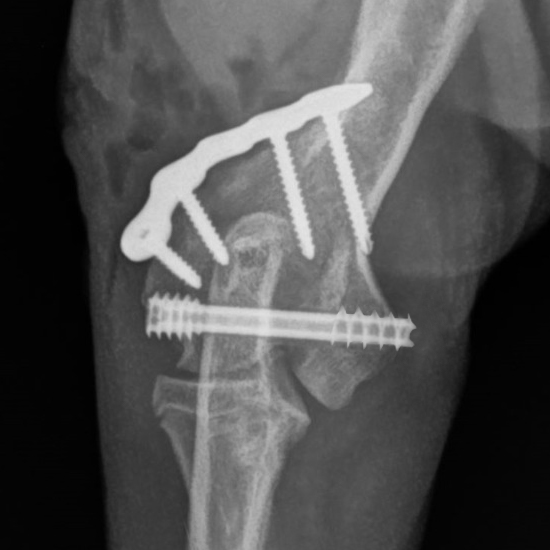

This course will explore the cannulated headless compression screw system, including its design, materials, and surgical applications. Participants will gain insights into the indications for these implants, such as elbow condylar fractures, ununited anconeal process (UAP), and hip procedures.

- Identify appropriate clinical indications for the use of headless compression screws, including elbow condylar fractures, ununited anconeal process (UAP), and hip procedures.